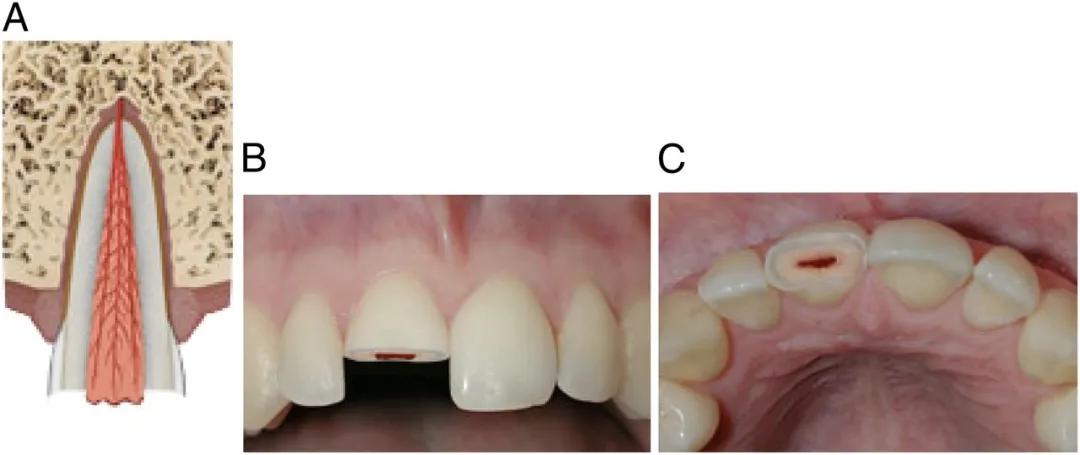

摔歪的牙齿通常是牙齿尖往里(舌侧方向)歪。

侧脱位

严重的牙齿可能摔“短”一截,甚至摔没了,整颗牙直接“楔”进牙槽骨里。

入侵式脱位

摔歪的牙齿,一般伴有疼痛、松动、出血,同时出现咬合障碍,家长没有什么急救方法,能做的就是尽快就诊。

脱位幅度小的,医生可能会什么都不做,等牙齿自己复位;也可能手动把牙齿复位,然后等它自己长好;严重的,可能上夹板固定,跟处理骨折一样;再严重的,可能直接拔掉。